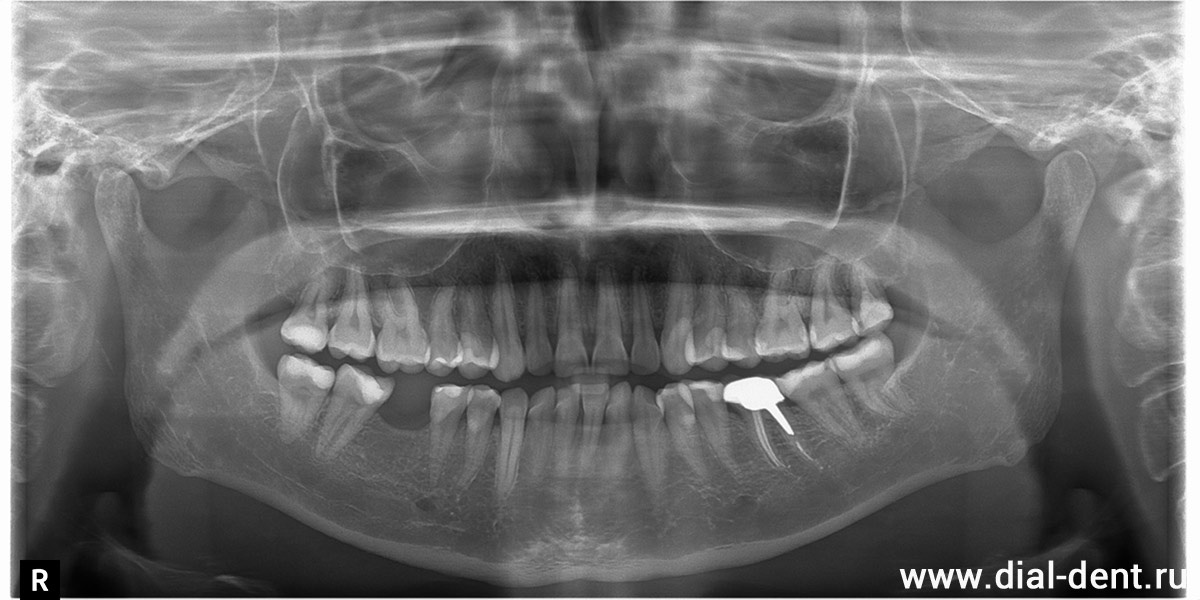

Стоматолог-ортопед направил пациентку на консультацию к ортодонту, стоматологу-терапевту и хирургу-имплантологу, чтобы составить план комплексного лечения. Выполнена компьютерная томография зубов:

КТ зубов до начала лечения